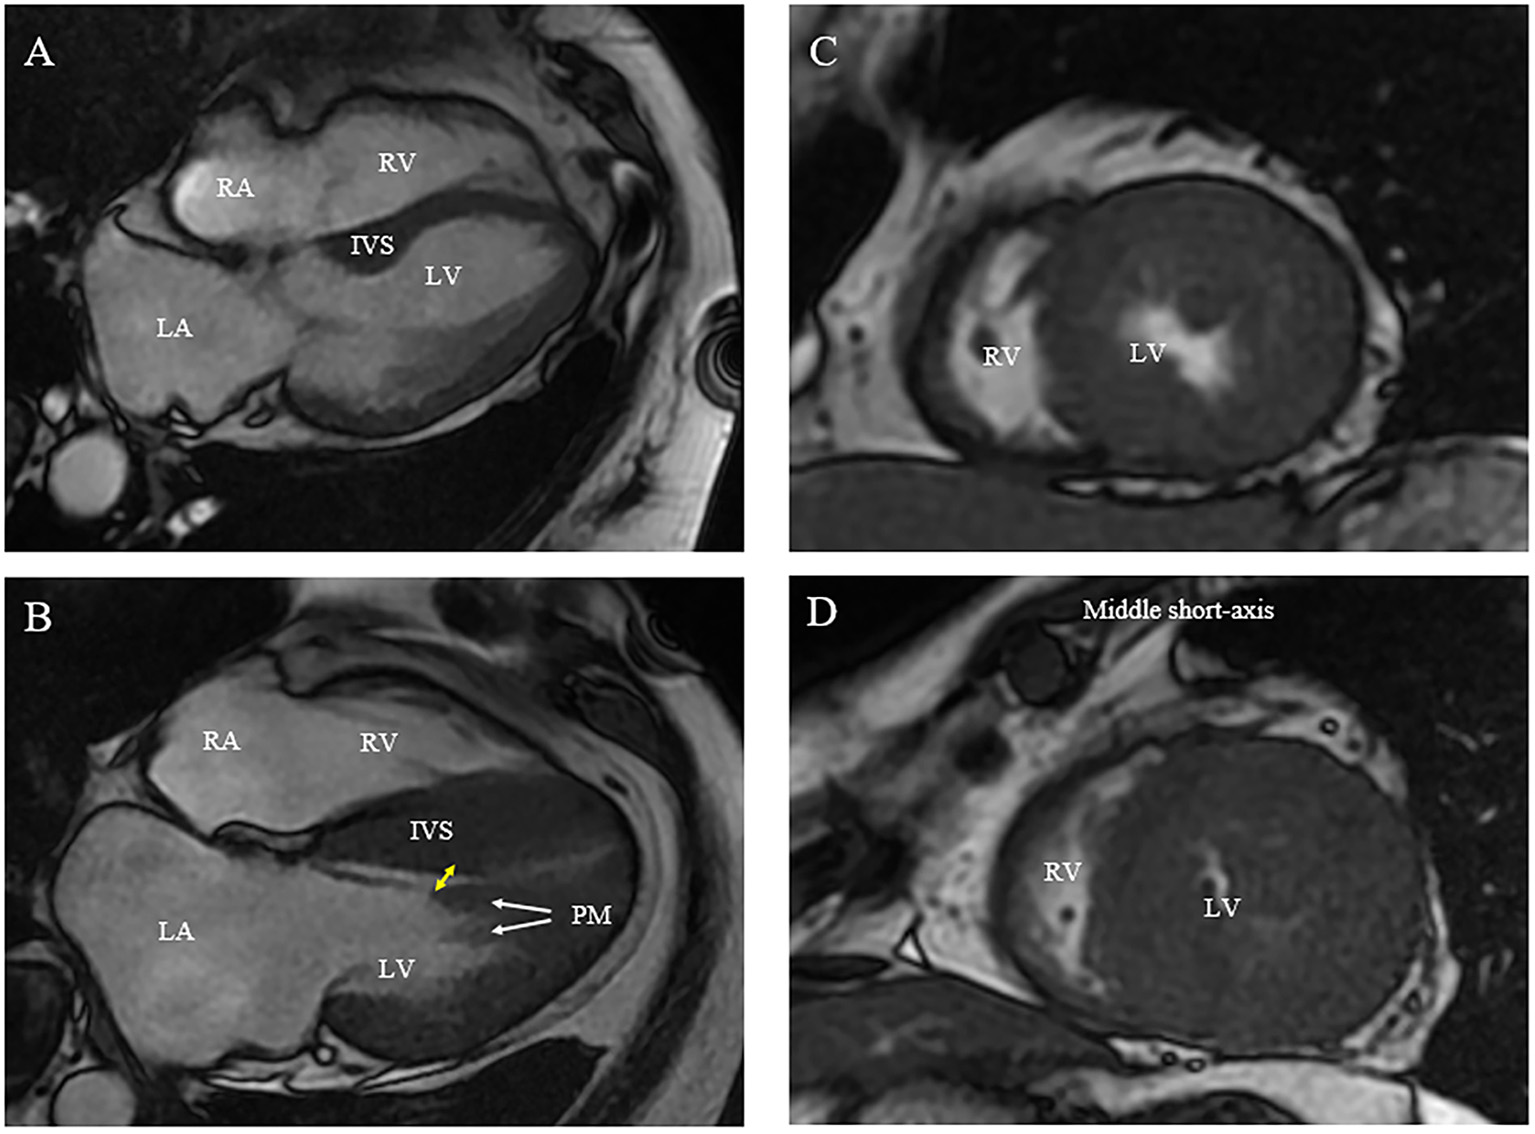

Figure 2

Morphologic abnormalities of papillary muscle (PM) contributing to outflow tract obstruction [(A) normal; (B) abnormal]. (A,B) On CMR, hypertrophied and apically displaced papillary muscle (white arrows) with superior head (yellow arrow) in close proximity to the bulged septum, positioning mitral valve plane toward ventricular septum compared with normal positioned PM (B). (C,D) As compared with a relatively normal papillary muscle object (C), CMR end-systolic image presents a severely narrowed LV cavity in patient with hypertrophied papillary muscle (D).